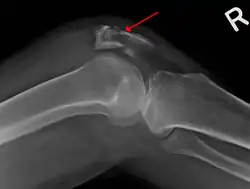

Comminuted fracture of patella -

Osteochondral fracture of patella -

| A fracture of the patella seen on a lateral view | |